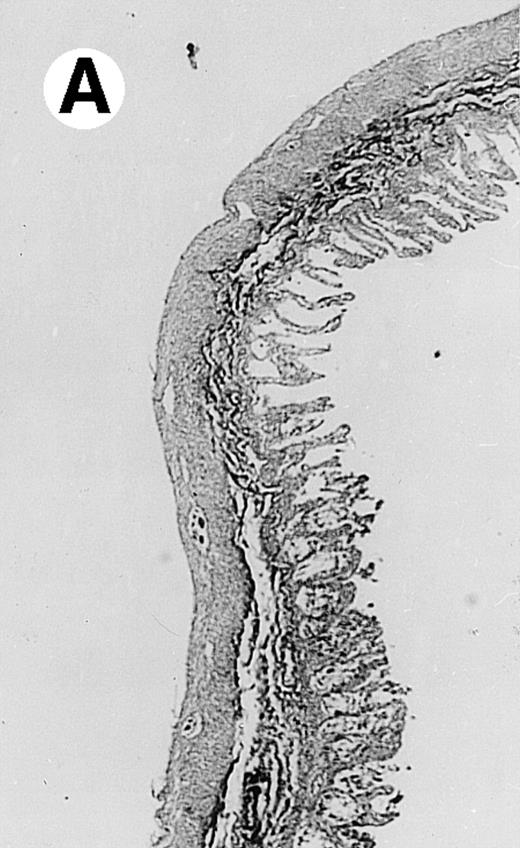

Pathologic findings in the small and large intestine were strikingly different depending on the treatment group. Figure 2A shows a representative pathologic sample from an animal assigned to the control group. Marked thinning of the bowel wall and extensive areas of epithelial cell sloughing was noted. Animals randomized to rhG-CSF treatment had minimal improvement in histologic findings with focal regions of preserved epithelium (Fig2B). Animals randomized to the rhIL-11 group showed substantial improvement with thickening of the epithelial layer and preservation of mucosal cell integrity (Fig 2C). Animals receiving both rhG-CSF and rhIL-11 had the most favorable histologic findings with normal mucosal thickness, minimal inflammatory changes, and preserved tissue architecture (Fig 2D). The composite analysis of the gastrointestinal pathology is provided in Table 1.

Histopathology of small intestinal mucosa cut in transection from an animal in each treatment group (study day 8). The upper panel (row 1) is a low power view (original magnification × 57); the lower panel (row 2) is a high power view (original magnification × 144). Note the diffuse thinning and necrosis of the mucosa with sloughing of intestinal epithelial cells in the control animal (A). There is progressive recovery of the thickness of the mucosa, reduction in inflammatory changes, and improved epithelial architecture with rhG-CSF (B), rhIL-11 (C), and combination therapy with rhG-CSF+IL-11 (D).